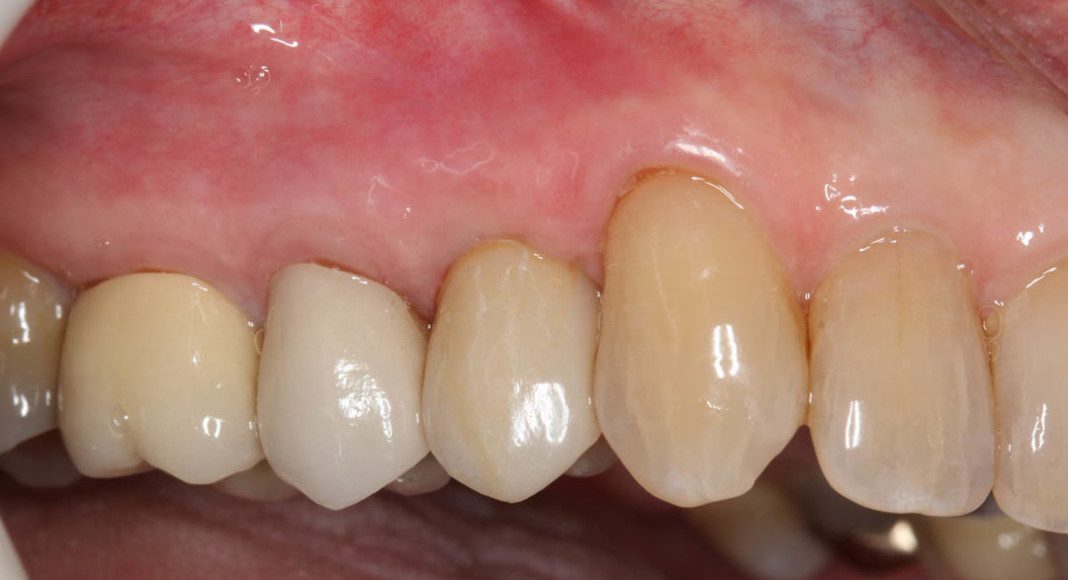

Though not obvious on the x-ray, this patient has fractured his upper right 1st premolar. Treatment plan: Extract tooth, place implant, fabricate an immediate, screw retained, temporary implant crown. Patient will never need to wear a removable partial or go without a tooth.